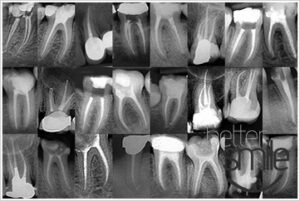

W przypadku próchnicy głębokiej dochodzi do stanu zapalnego miazgi, ząb wymaga leczenia kanałowego. Nawet wąskie i zakrzywione kanały można udrożnić wykorzystując narzędzia ręczne, pilniki mechaniczne (np. ProTaper), pilniki ultradźwiękowe oraz wielokrotne przepłukiwanie śródzabiegowe. Długość korzeni ustalamy endometrem elektronicznym Raypex5. Dokładnie opracowany kanał zęba zostaje na całej swej długość wypełniony uplastycznioną masą – gutaperką, podawaną z pistoletu, a efekt końcowy prawidłowo wykonanego leczenia potwierdzamy zdjęciem rtg.

- Stosowane przez nas narzędzia są wykonane ze stopu niklu i tytanu co zapewnia im bardzo dużą giętkość i niełamliwość.

- Przeleczyliśmy kanałowo ponad 2 tyś. zębów, można nam zaufać.